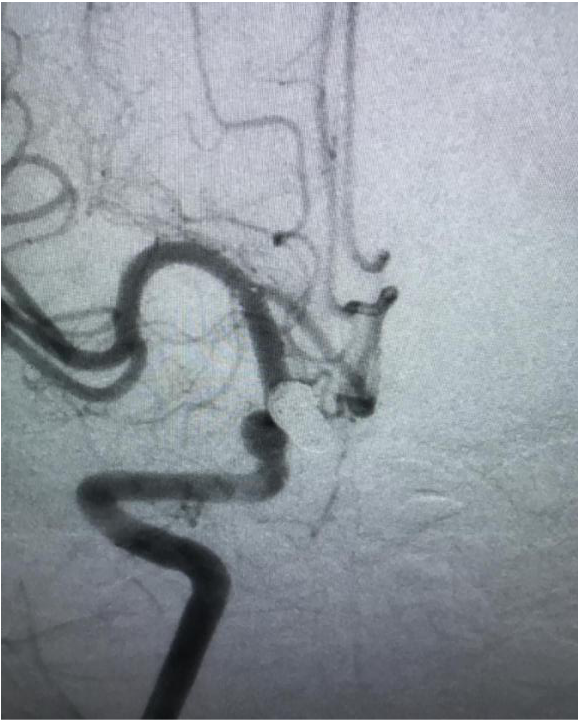

(治疗前三维造影)

入院后第二天,赵师傅被送入杂合手术室,脑血管病组团队医师们登台手术。医生们从赵师傅右股动脉穿刺,将导丝从股动脉、腹主动脉、胸主动脉一路插至颅内载瘤动脉,再运用微导管技术将弹簧圈送到动脉瘤腔内,栓塞瘤腔,在主干血管内置入一枚支架,稳固弹簧圈的同时保留了正常血管的血流。经两个小时手术,赵师傅脑内的动脉瘤被完全填塞封堵。